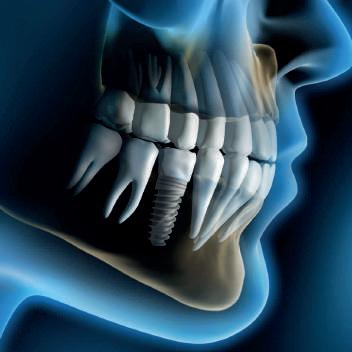

DENTE O IMPIANTO?

14.30 La riabilitazione dei pazienti parodontali: impianti o denti?